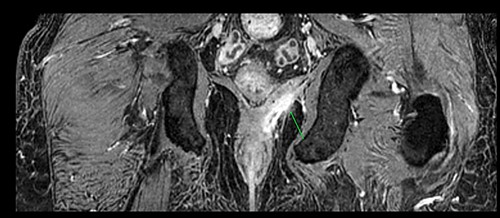

A 61-year-old diabetic patient was admitted from emergency department with septic signs; fever of 39°C, white blood cell count of 20.000/μl, C-reactive protein levels of 156 mg/l and blood glucose levels of 280 mg/dl. For the past 10 days, the patient has noted malodorous anorectal pus discharge, as well as anorectal and suprapubic pain. During macroscopic examination of the perineum, a left-sided abscess in the ischiorectal fossa was identified, with an opening lateral to the sphincteric anal system draining pus. Subsequent digital rectal examination of the anorectal canal could not be completed due to pain, but the initial effort revealed large amounts of pus discharged from anorectal canal. CT and MRI demonstrated an abscess situated in the left ischiorectal fossa and a large supralevator abscess extending cephalad in the extraperitoneal space with a long fistulous tract containing liquid (pus) and gas bubbles, up to the suprapubic area, where erythema with an undulating pus collection below the skin was noted; laterally the pus collection extended up to the left ilio-femoral vessel canal. CT (Fig. 1) and MRI (Fig. 2) were conclusive for the above entity, aptly demonstrating the presence of the two abscess cavities. Proctoscopy under general anesthesia revealed a protruding extra-rectal mass in the left lateral and inferior segment of the rectal ampulla. Finger pressure at this point was accompanied with pus exit from the posterior dentate line of the anal canal at 6 o’clock, through an opening of 1–2 mm in size. Surgery was addressed in three main locations of the pus collection with goal to drain completely the pus; the abscess of the left ischiorectal fossa was drained with enlargement of the external opening of fistula; after curettage, debridement and washing of abscess cavity, a probe was used to detect the internal opening exactly at the posterior dentate line at 6 o’clock. The fistula was characterized as full trans-sphincteric with an extra-sphincteric component in the ischiorectal fossa leading up to the skin. A non-cutting vessel loop drainage seton was then placed. The supralevator abscess was then easily drained from the opening in the posterior dentate line by finger pressure in the left rectal ampulla. A probe following the route of the internal opening upwards to supralevator space led to pus evacuation, allowing this space to be thoroughly washed with water saline solution, using a syringe with a vein catheter. Finally, the suprapubic area was drained with a small stab incision, followed by washing with normal saline. There was a prompt recovery postoperatively, tight control of blood glucose levels, whereas a CT performed 7 days postoperatively (Fig. 3), demonstrated an empty supralevator space with a fistulous tract still present, albeit with significant regression of inflammatory changes.

CT of the lower pelvis; supralevator abscess, with extension upward in touch with the left ilio-femoral vessels. The abscess cavity is shown approaching the skin with a long fistulous tract containing liquid (pus) and gas bubbles (green arrow).